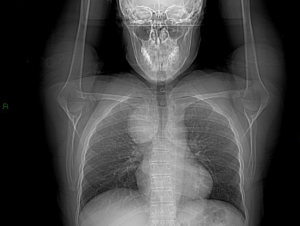

Herein we present here a case of SVCS caused by an ectopic thyroid lobe mimicking a mediastinal tumor. A 42-year-old woman went to our unit with facial flush and swelling and headache. Patient medical history was unremarkable, no smoking habits was remarked. During the neck examination a right lymphadenopathy was palpable and goiter thyroid was observed on the left side. An unclear mediastinal mass was observed at chest radiography associated with a tracheal compression (Figure 1). A Computed Tomography was performed (Figure 2). A scintigraphy was performed and a thyroid goiter was diagnosed. The patient underwent to surgical excision of the tumoral mass by sternotomy incision associating a thyroidectomy. Surgery was uneventful and patient was discharged on post operative day 7. Thyroid tissue was observed at pathology exam. Mediastinal ectopic thyroid tissue is rare. This finding is an embryological abnormality characterized by the occurrence of thyroid tissue in a site other than its usual location. The Ectopic tissues are currently described in literature and it is a result of a migration defect during embryological development or after a trauma (2,3). SVCS is in near of 97% of cases caused by malignancy (1) and thyroid cancer as primary etiology is extremely rare (4). In our case a secondary goiter of ectopic thyroid tissue was the cause of SVCS; surgical treatment was a therapeutic cure for the patient.